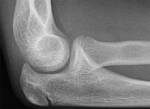

- ant fat pad normally seen in children

- post fat pad NOT usually seen as buried in intercondylar fossa

- unlikely intra-articular injury if fat pad sign not +ve

- likely occult # if fat pad sign +ve and # not visible